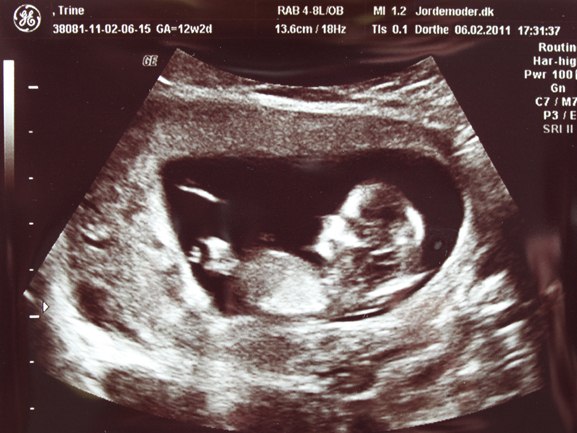

Jeg er i dag 12+2 og kæresten og jeg havde købt os til en scanning da han ikke kan komme med når jeg skal til NF på Tirsdag.. hehe..

Da vi kom derind kom der hurtigt billede på og lige der kunne vi se den meste fantastiske lille skabning.

Det var helt vildt at se den lille en som der ligger derinde og hygger sig. Den havde vist også lidt hikke, der kom der hvert fald nogle hop en gang imellem, vi fik også et lille vink, og to 2 havde den også vendt ryggen til os..

Hende som scannede os sagde at alting så såååå fint ud.. den målte 5,7 cm fra hovede til hale, og størrelse på hovedet og lår ben var også super flot

Iiih hvor var det virkelig vildt at se den lille trut der ligger der inde..